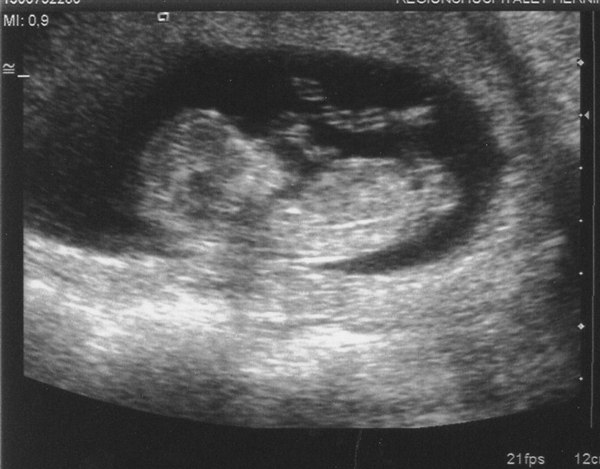

Det var bare så skønt at se den lille bebs tumle rundt derinde, den viste sig rigtig frem, så vi så både de lange fine ben, arme og fingre

Og alt var heldigvis som det skulle være, tallene var fine, så nu kan jeg nyde det uden at bekymre mig alt for meget

Her er vores lille bebs

Vedhæftede fotos (klik for at se i fuld størrelse)